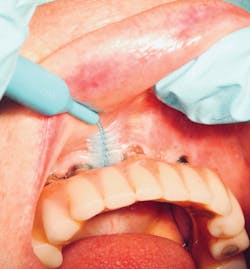

Interdental brushes

A staple for home care in all periodontal patients, the interdental brush (bottle brush; figure 10) is crucial for the care of implant embrasures, especially when they are wide. Unlike a natural tooth with a wide platform above the furcations, posterior implants have a wide tooth perched on a narrow post. This creates two nooks that invite both plaque to harbor and food to impact. A solution is to insert the widest interproximal brush that will comfortably fit in the space. The brush not only provides tissue stimulation but also removes plaque and debris instantly. Dipping the brush in an antiseptic increases the benefit.